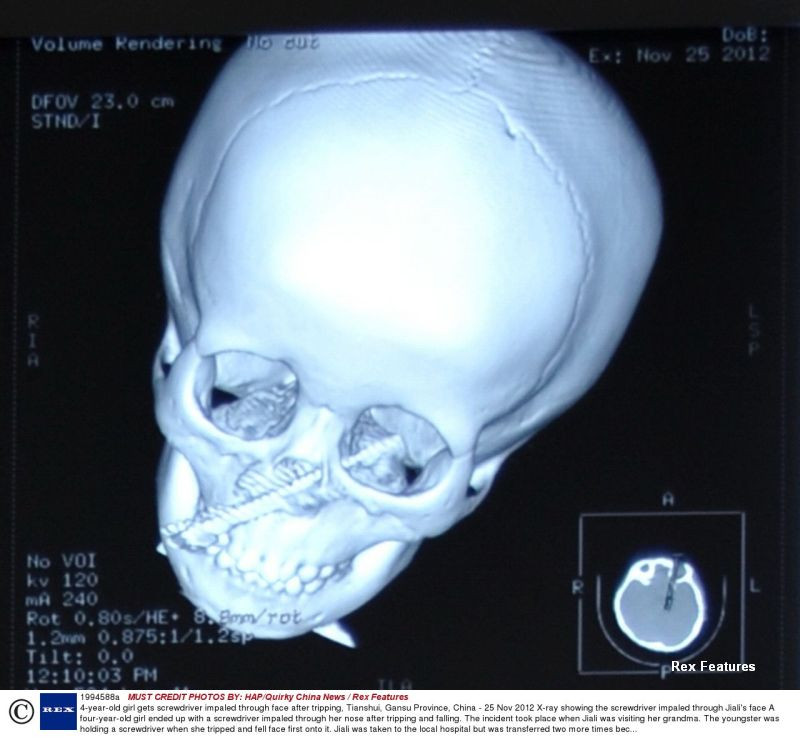

IMAGINI SOCANTE. O fetita de 4 ani a supravietuit miraculos dupa ce i-a intrat o surubelnita in fata

Jiali Gang, o fetita care traieste in provincia chineza Gansu, a reusit sa scape cu viata dupa ce, in urma unui accident, o surubelnita i s-a infipt in fata.

Conform Mirror, Jiali se juca acasa la bunica ei cu unealta, iar la un moment dat s-a impiedicat si a cazut cu fata in ea.

Surubelnita i-a patruns prin nas si s-a oprit la doar 2 milimetri de creier.

Fetita a fost transportata rapid la spital, unde medicii au operat-o cu succes si i-au salvat viata.